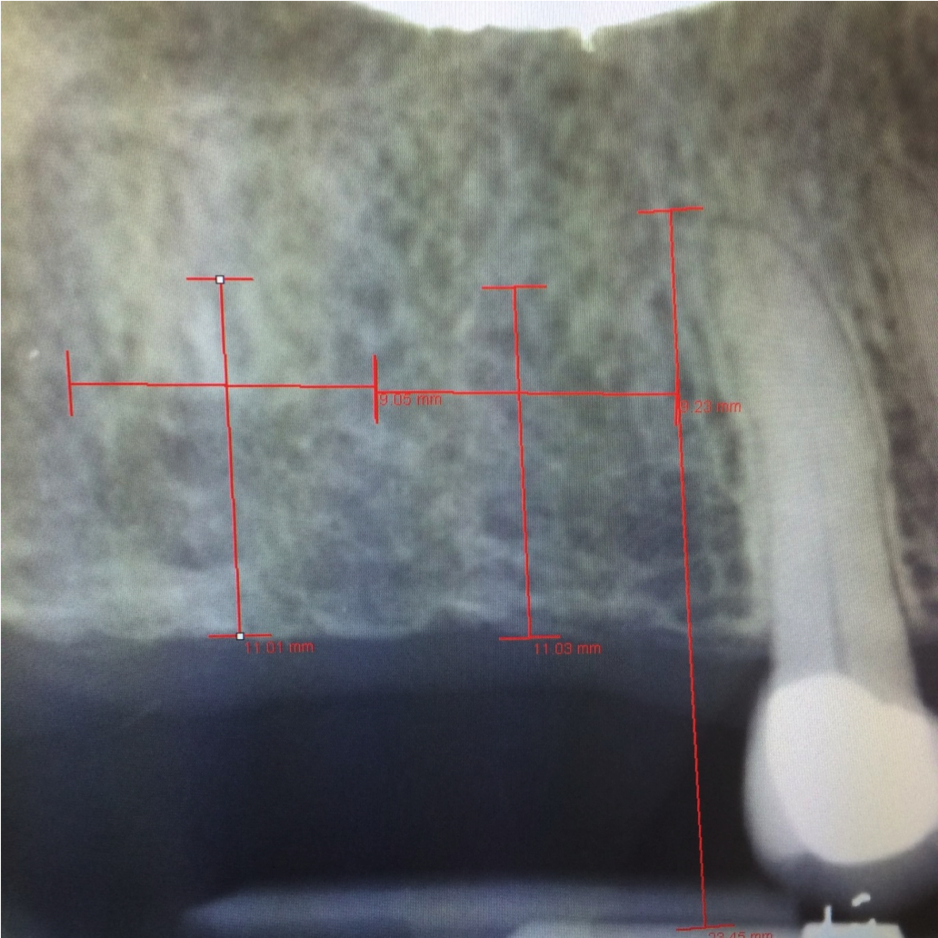

In this case, the patient’s right maxillary first molar had been extracted, and the site was grafted. The periapical radiograph taken after 6 months of healing indicated the presence of dense bone (Figure 11). There was also ample attached mucosa (Figure 12). Impressions were taken, a diagnostic cast was made, and a wax-up of the restoration was placed in the model (Figure 13). To make the radiographic guide for this case, a silicone putty index was created over the diagnostic wax-up, as described earlier. A panoramic radiograph and a CBCT scan (Figure 14) were taken with the radiographic guide in place; the guide post in the index can clearly be seen.

After merging the digitized cast and CBCT scan data, the dimensions of the site were evaluated. Almost 11 mm of bone was present below the maxillary sinus, and the width of the site was 8.5 mm, which was sufficient space to enable creation of a screw-retained restoration. To facilitate the screw access, a decision was made to position the implant slightly lingually, while maintaining the implant within the housing of buccolingual plate.

Fig 14. Panoramic radiograph and CBCT scan taken with radiographic guide in place.

Figure 14